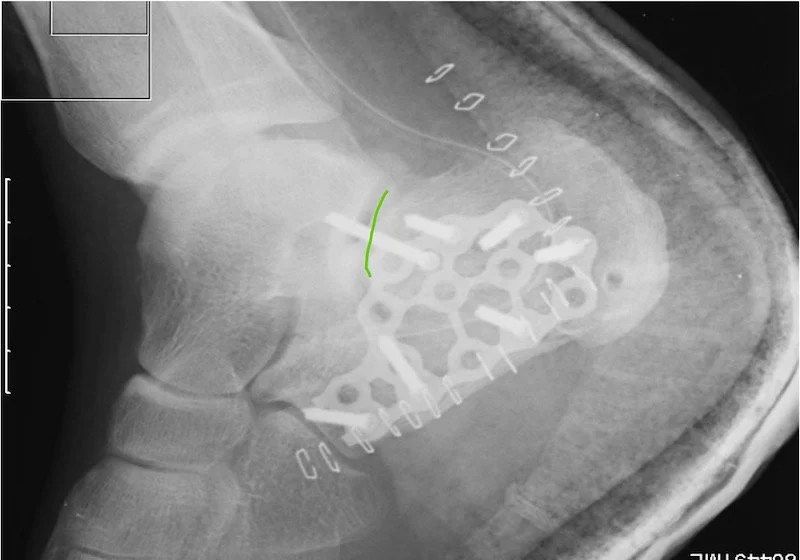

You can see in this picture during surgery that the bone has a black dark area through it , thats how the fracture line looks. When these bones break the bone is crushed into itself and we essentially lose bone shape. During surgery we put it all together as much as possible. Then we apply a large plate that you can see in the next photo tp hold all of the fragments together. As you can see this is a large incision, we prefer not to do it this way so 90 percent of the time we are able to use or minimal incision technique for these bone repairs.

Here is an xray of the same foot with a plate attached after surgery to realign the joint and bones. You can see the curved green line- we were able to put the subtalar joint back into alignment to hopefully prevent progression of arthritis and pain.